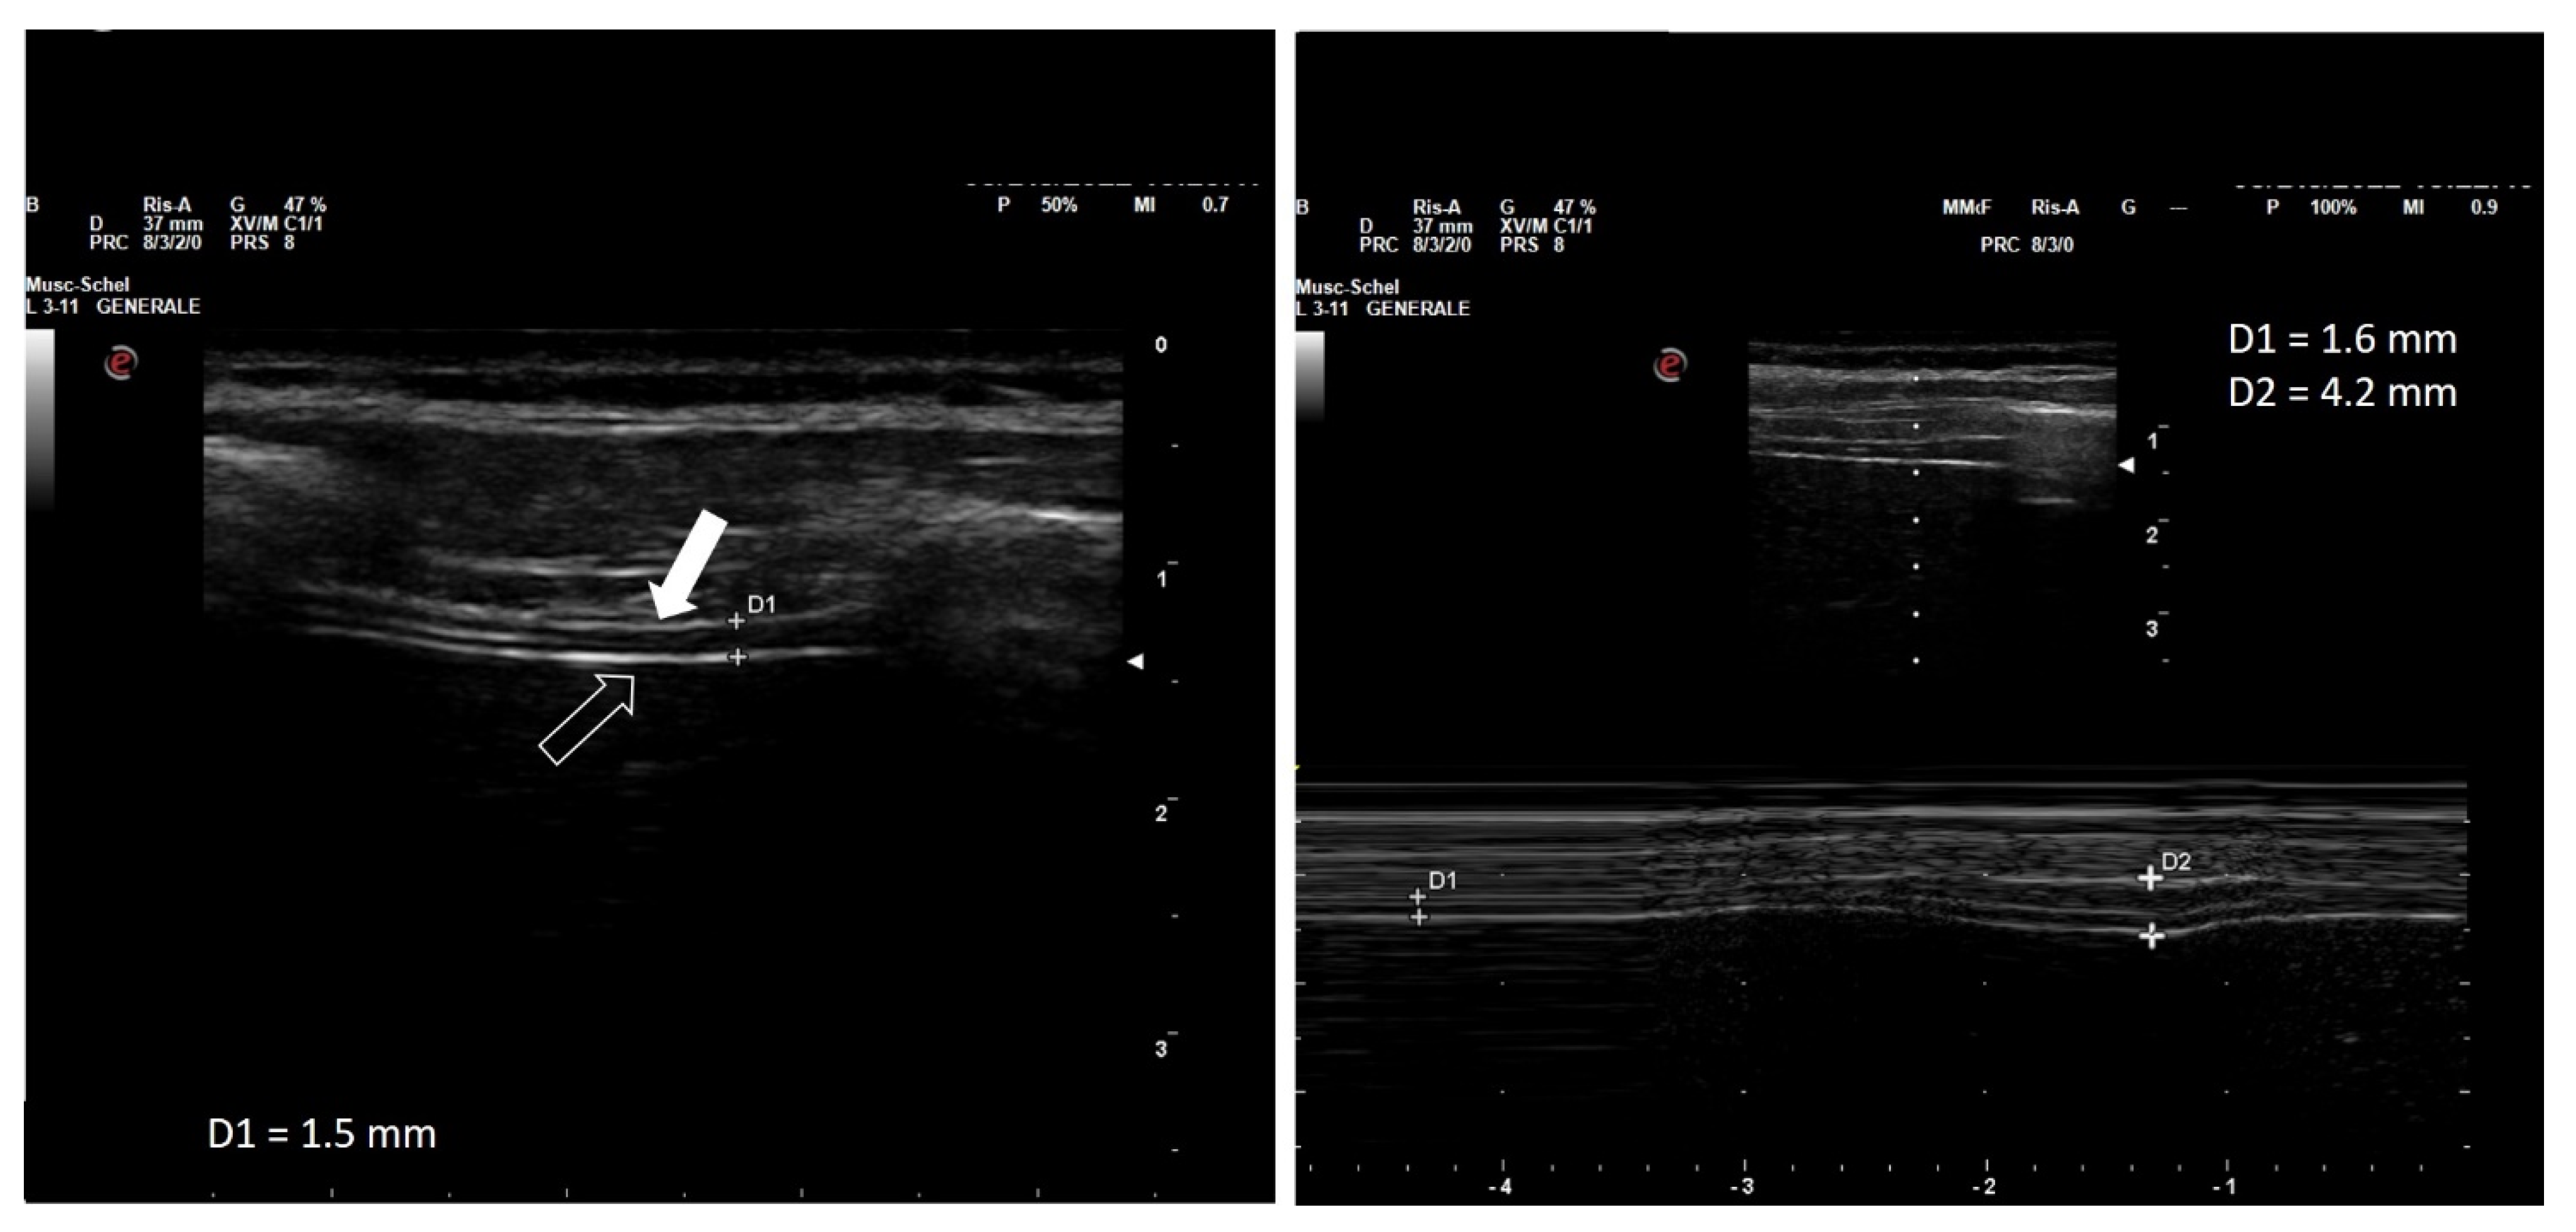

The diaphragm can be visualized as a three-layered band, which includes (from the outer to the inner layer) the hyperechogenic diaphragmatic pleura, the relatively hypoechogenic muscle, and the hyperechogenic peritoneal pleura (Figure 1).

Figure 1.

Thickness of the right hemi-diaphragm at the zone of opposition (left panel) and diaphragm thickening during maximal inspiration (right panel) in a healthy woman in her thirties while semi-recumbent. Left panel: note the two hyperechoic lines (arrows) representing the peritoneum (empty arrow) and parietal pleura (filled arrow). The measured thickness (D1) is 1.5 mm. Right panel: the same diaphragmatic region during maximal inspiration from resting volume to total lung capacity. Diaphragmatic thickening is examined in motion mode (M-Mode). During full inspiration, thickness increases from 1.6 (D1) to 4.2 mm (D2), equal to a thickening fraction of 162%. Own image.

The distance between the inner margins of the diaphragmatic and peritoneal sheets is defined as the thickness of the diaphragm, the normal median (interquartile range) value of which is highly variable, with the majority of measurements ranging 3.3 (1.3–7.6) mm. Thickness is lower in female than in male patients, and is positively correlated to height and body weight, but independent of age [24,25]. Moreover, it should be noted that diaphragm thickness is increased in standing and sitting position compared with the recumbent position [26], and that it is greater at the lower intercostal spaces [27]. Diaphragm thickness at rest in healthy patients is highly variable, ranging from 1.2 to 11.8 mm among individuals, with group mean values of 1.6 to 3.4 mm and a lower limit of normal (LLN) in adults ranging from 0.80 to 1.60 mm [21].

Variations of the thickness of the diaphragm during the respiratory cycle are inversely proportional to variations of its transverse surface, which results from its contractile activity. Since the volume of the muscle is constant, the shortening and flattening of the diaphragm during contraction is associated by a proportional increase in its thickness (Figure 1) [22]. The percentage by which the thickness increases from the end of exhalation to the end of inspiration is called the thickening fraction, while the ratio between the end-inspiratory and the end-expiratory thickness is called the thickening ratio [28]. Similar to diaphragmatic thickness, the thickening fraction also shows wide variability in different individuals, with reference values ranging from 60% to 260% (left hemidiaphragm) and from 57 to 200% (right hemidiaphragm) while seated [28].